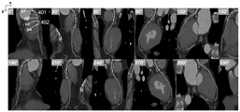

FIG. 2 shows a set of differently angled 2D vascular medical images corresponding to a 3D vascular medical image according to an embodiment of the present application;

In some embodiments, the more regularly the target is distributed in the vessel or the more regularly the shape of the target, the greater the spacing of the angles, the target including at least one of a vascular lesion (such as, but not limited to, a plaque, a stenosis, a myocardial bridge, etc.) and a vascular interventional instrument. Therefore, selection can be performed according to the actual situation of the blood vessel, the detection efficiency is further improved, and the data volume to be processed is reduced. For example, if the object to be detected is a plaque, the CPR exhibits a large difference for the lesion for each angle, the angular separation D of the 2D vascular medical image may be set small, e.g. 0-30 degrees, such as 30 degrees as shown in fig. 2. In fig. 2, the angles are uniformly distributed, but the angle distribution may not be uniform, and 2 or more angles may be selected according to the property of the object. Therefore, the plaque can be seen from more angles as much as possible, and the condition that the judgment of the plaque property is wrong due to omission of certain angles can be avoided as much as possible. While for each angle CPR the task that shows little difference to the lesion, e.g. the task of stent detection, D can be set to be larger (e.g. D =60 degrees) because the stent is a regular cylinder, and at any angle of the vessel, it assumes a consistent shape, and there is no need to sample many angles, because there is limited improvement in the accuracy of detection.

In some embodiments, 2D image target detection techniques are employed to perform target detection on the 2D vascular medical images at each angle. The detection techniques herein may be based on deep learning, or may be based on conventional algorithms. In some embodiments, the 2D object detection result includes a 2D checkbox of the object and position information of the 2D checkbox. In some embodiments, the 2D detection box of the target may be a horizontal box, which may be defined by the coordinates of the center point of the box and the height and width of the box, and may also be defined by the coordinates of the upper left corner (x 1, y 1) and the lower right corner (x 2, y 2) of the box, as shown in fig. 3 (a). In some embodiments, the 2D detection frame of the object may also be an oblique frame, and as shown in fig. 3(b), the definition of the oblique frame may be based on the definition of the horizontal frame, and an angle parameter α between the frame and the coordinate axis (horizontal axis or vertical axis) may be added. As shown in fig. 4, in a task of detecting an object such as plaque, for any one blood vessel, for example, a Left Anterior Descending (LAD) blood vessel, an object in a 2D blood vessel medical image at each angle is detected by using a 2D image object detection technique, and is marked using oblique frames, for example, a firstobject detection frame 401 and a secondobject detection frame 402. As shown in fig. 4, the firstobject detection frame 401 and the secondobject detection frame 402 are object regions detected in CPR image data sets at different angles. The intersection points of the boundaries of the target detection frames and the central line are the starting point and the end point of the target, and can also be called as an upper limit of a longitudinal coordinate and a lower limit of the longitudinal coordinate. In the CPR image data set corresponding to an angle of 0 degree in fig. 4, p1 and p2 represent the upper limit and the lower limit of the vertical coordinate of the firstobject detection frame 401, respectively, and p3 and p4 represent the upper limit and the lower limit of the vertical coordinate of the secondobject detection frame 402, respectively. From the viewpoint of the positional information, of p1 and p2, a point p1 having a small y value (longitudinal coordinate value) is the upper limit of the longitudinal coordinate of the firstobject detection frame 401, a point p2 having a large y value (longitudinal coordinate value) is the lower limit of the longitudinal coordinate of the firstobject detection frame 401, and similarly, p3 is the upper limit of the longitudinal coordinate of the secondobject detection frame 402, and p4 is the lower limit of the longitudinal coordinate of the secondobject detection frame 402. The longitudinal coordinate information of p1, p2, p3 and p4 can be used as reference information to efficiently and accurately map the 2D detection result back to the 3D central line in the 3D blood vessel medical image.

More specifically, fig. 5 shows an exemplary mapping of 2D object detection results in a 2D vessel medical image at an angle of 0 degrees to the 3D centerline of the vessel. The upper and lower longitudinal coordinate limits of the detected frame of the object detected in the 2D vascular medical image can be used to calculate its position in the 3D centerline of the 3D vascular medical image. For example, the object detection frames of the firstobject detection frame 401 and the secondobject detection frame 402 divide the 2D blood vessel medical image into a plurality of image layers according to the vertical coordinate, and each image layer corresponds to the vertical coordinate value of the unit length. Specifically, the longitudinal length is 10 unit lengths, and the 2D blood vessel medical image is divided into 10 image layers, each image layer corresponding to a longitudinal coordinatevalue 1 of 1 unit length. As shown in fig. 5, the upper limit p1 of the vertical coordinate of the firstobject detection frame 401 is 23 in the vertical coordinate y1, and the lower limit p2 of the vertical coordinate of the firstobject detection frame 401 is 72 in the vertical coordinatey 2. Calculating the number of 2D centerline points in the image layer with longitudinal coordinates 0 through 22 to be 39, p1 corresponds to the 40 th (i.e., 39+ 1) point in the 3D centerline. Calculating the number of 2D centerline points in the image layer with longitudinal coordinate 0 to longitudinal coordinate 71 to be 94, p2 corresponds to the 95 th point in the 3D centerline. To this end, it can be shown that the firstobject detection frame 401 defined by p1 and p2 in the 2D vascular medical image corresponds to: the first 3Dobject detection frame 501 from the 40 th 3D center point to the 95 th 3D center point is p1_ index =40, p2_ index = 95. Similarly, the upper limit p3 of the longitudinal coordinate of the secondobject detection frame 402 is 88 in the longitudinal coordinate y3, the lower limit p4 of the longitudinal coordinate is 108 in the longitudinal coordinate y4, and the corresponding second 3Dobject detection frame 502 is from the 105 th 3D center point to the 125 th 3D center point, i.e., the position along the 3D center line is p3_ index =105, and p4_ index = 125.

As shown in fig. 4, in the same target detection process such as a lesion, there may be a target to be detected in 2D blood vessel medical images of a plurality of angles at the same time, and there may be a difference between the longitudinal coordinate value of the target to be detected and the detection frame thereof and the size of the 2D blood vessel medical image at each angle.

After the 2D target detection result of the 2D blood vessel medical image of each angle is mapped to the 3D center line of the blood vessel according to the mapping method described above, a plurality of overlapped or partially overlapped detection frame coverage results appear in the same area on the 3D center line, as shown in a first target detectionframe coverage area 601 and a second target detectionframe coverage area 602 in fig. 6 (a). Therefore, as shown in fig. 6(b), the number of times each 3D center line point in each area is covered by the firstobject detection frame 401 or the secondobject detection frame 402 may be 1 or an integer greater than 1, the cumulative number of times of covering of each point along the 3D center line in the first object detectionframe covering area 603 is 1, 7, 10, 12, 6, 5 in this order, and the cumulative number of times of covering of each point along the 3D center line in the second object detectionframe covering area 604 is 2, 7, 8, 3 in this order.

As shown in fig. 6(b) and 6(c), the voting mechanism includes: assuming that the number of detection frames obtained by a certain lesion area is X in the 3D coordinate system, statistics may be performed on all center line points of the lesion area (connected domain), and center line points which are covered by different frames for a cumulative number of times greater than p X are considered as lesions, and other points in the area are not considered as lesions. And p is a probability value of 0-1, which can be set by a user according to tasks, and X represents the maximum value on the central line in any lesion area. For example, in the plaque detection task, p =0.2 may be set, and as can be seen from fig. 4 and 5, the plaque (or the first object detection frame) defined by p1 and p2 cumulatively covers the 3D blood vessel medical image 12 times. Therefore, the maximum value corresponding to the plaque on the 3D centerline is X =12, and then, on the 3D centerline, all the points in the 3D centerline with the 3D centerline value greater than 0.2 × 12=2.4 are considered as lesions, and the rest are not, as shown in the firsttarget detection region 605; the plaque (or second object detection box) defined by p3 and p4 is cumulatively covered 8 times on the 3D vascular medical image, and X =8, then values with 3D centerline values greater than 0.2X 8=1.6 in this region are considered lesions, and the rest are not, as indicated by the secondobject detection region 606, considered lesions.